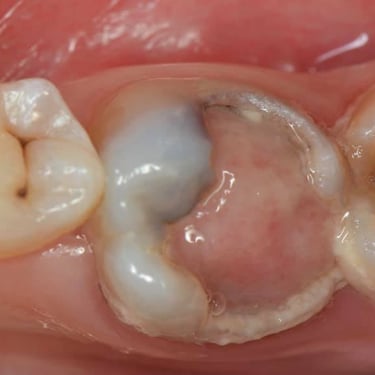

Pulpitis Crónica Hiperplásica

La pulpitis crónica hiperplásica es una inflamación de la pulpa con crecimiento excesivo de tejido pulpar a través de una caries abierta.

Los pacientes notan un tejido rojo que sobresale de la cavidad dental.

El tratamiento incluye la eliminación del tejido afectado y un tratamiento de conducto. Es crucial tratar la caries para evitar infecciones adicionales.